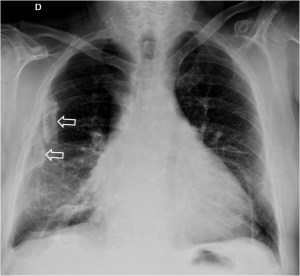

SIGNO DE LA HOJA DE ACEBO

Signo visible en la radiografía de tórax, que corresponde a placas pleurales calcificadas. Aunque las placas pleurales son amorfas o irregulares, su forma se ha comparado a la hoja del acebo (holly leaf sign). Se trata de calcificaciones bien definidas, de borde geográfico, que se localizan más frecuentemente en las porciones posterolaterales de los campos medios pulmonares. Pueden confundirse con patología parenquimatosa. La clave para identificarlas es reconocer la calcificación que no sigue el recorrido de las costillas ni la distribución broncovascular.

La imagen de TC muestra varias placas pleurales calcificads (flechas) en el mismo paciente de la radiografía.